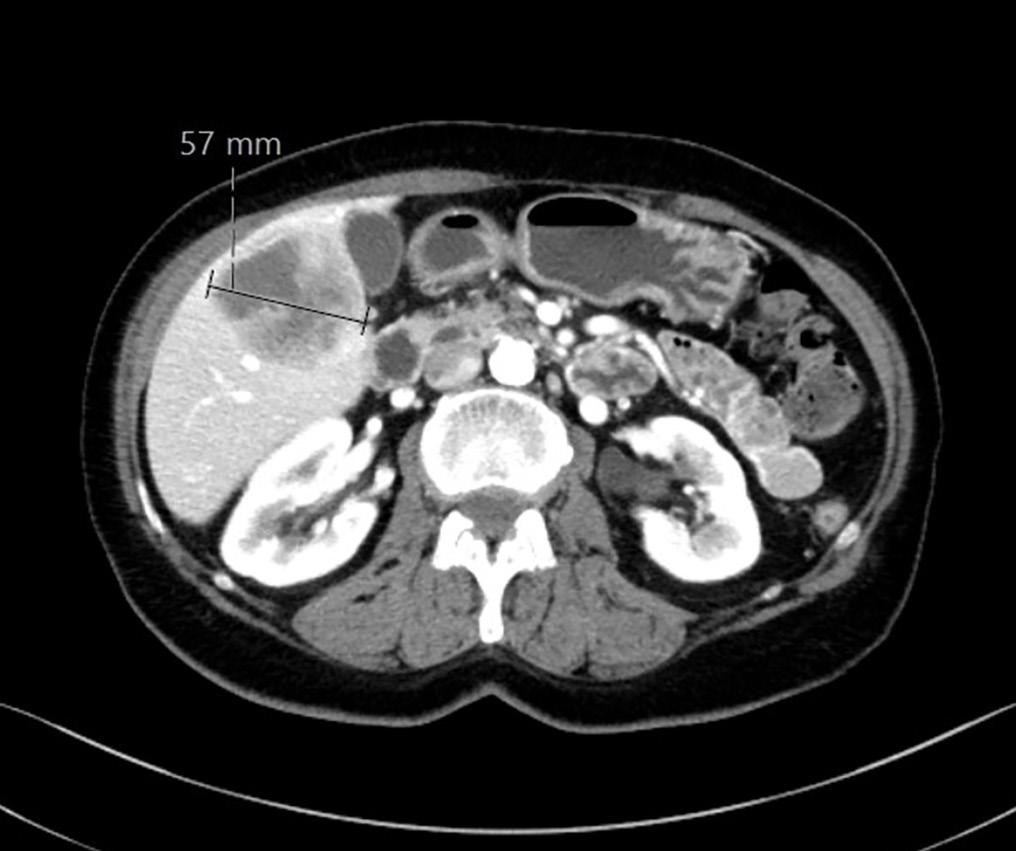

CT thorax/abdomen/bekken 16 måneder etter sykdomsdebut viste ingen tegn til persisterende sykdom. Imidlertid hadde pasienten fått smerter i skulder og 17 måneder etter sykdomsdebut ble det påvist en 4,5 cm stor metas-

2: MR høyre skulder 14 måneder etter sykdomsdebut viste metastase i humerus. Den ble initial strålebehandlet med noe bedring av smertene. Etter hvert tilkom det påny vekst og smerter, og pasienten ble operert med protese etter åtte måneder. Samtykke til publisering av røntgenbilde er innhentet fra pasientens ektemann da pasienten er død.

tase i humerus (Bilde 2). Biopsi bekreftet metastase fra anaplastisk karsinom. NTRAK 1-3 fusjon og RET fusjon/ mutasjon var negative. Pasienten fikk strålebehandling 4 Gy x 7 mot metastase i humerus. Medikasjon ble endret til encorafenib 150 mg og bimetinib 45 mg x 2. Åtte måneder senere ble hun operert med fjerning av tumor i humerus og implantasjon av skulderprotese på grunn av økende vekst og smerter.